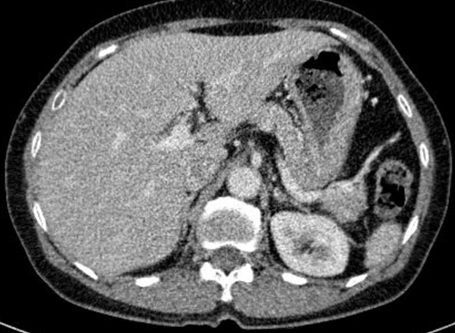

Cắt lớp vi tính bụng: Không phát hiện tổn thương bất thường.

Hình 4: Không phát hiện hình ảnh bất thường trên phim cắt lớp vi tính bụng.